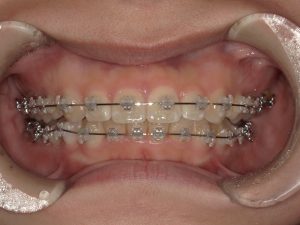

- 叢生、顎関係の不調和(Ⅱ級)、左側第二小臼歯部および第二大臼歯部鋏状咬合、下顎左右第三大臼歯の埋伏

- 主な使用装置

- マルチブラケット装置(+金属ワイヤー)

治療中の様子(マルチブラケット装置+金属ワイヤー)